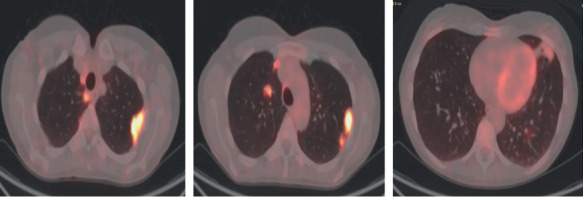

Primary Sjögren syndrome (pSS) is a systemic autoimmune disorder that principally affects the exocrine glands but can also affect systemic or extra-glandular sites. Approximately 65-80% of patients with Sjogren's demonstrate pulmonary involvement at the CT scan and pulmonary nodules (PNs) can be encountered as a common finding. We present the case of a 49-year-old woman admitted to the emergency department for chest pain and fever. The patient was diagnosed with pSS fourteen years prior and had never taken therapy or followed regular check-ups. At the HRTC were found PNs that were studied trough a CT-PET and a needle biopsy via CT guidance, which showed diffuse large B cell lymphoma. This case report underlies the importance of check-ups and the need for a multidisciplinary approach in the care of Sjögren's syndrome patients.